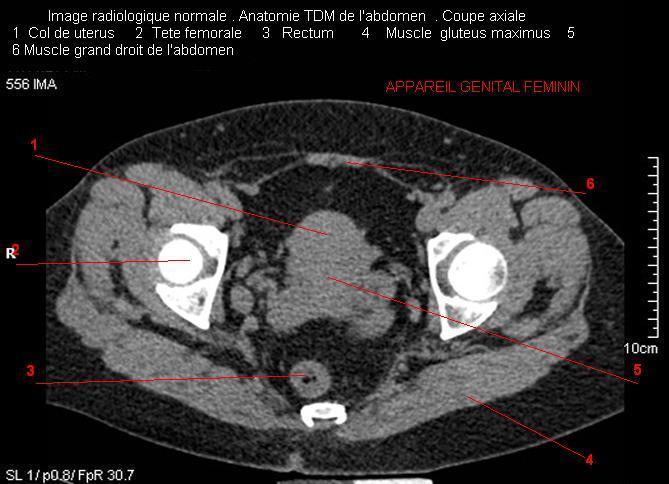

Images radiologique TDM normale de l'abdomen et tube digestif en coupe axiale ( CT scanner )  :

Coupe axiale     Coupe frontale      Coupe  sagitale